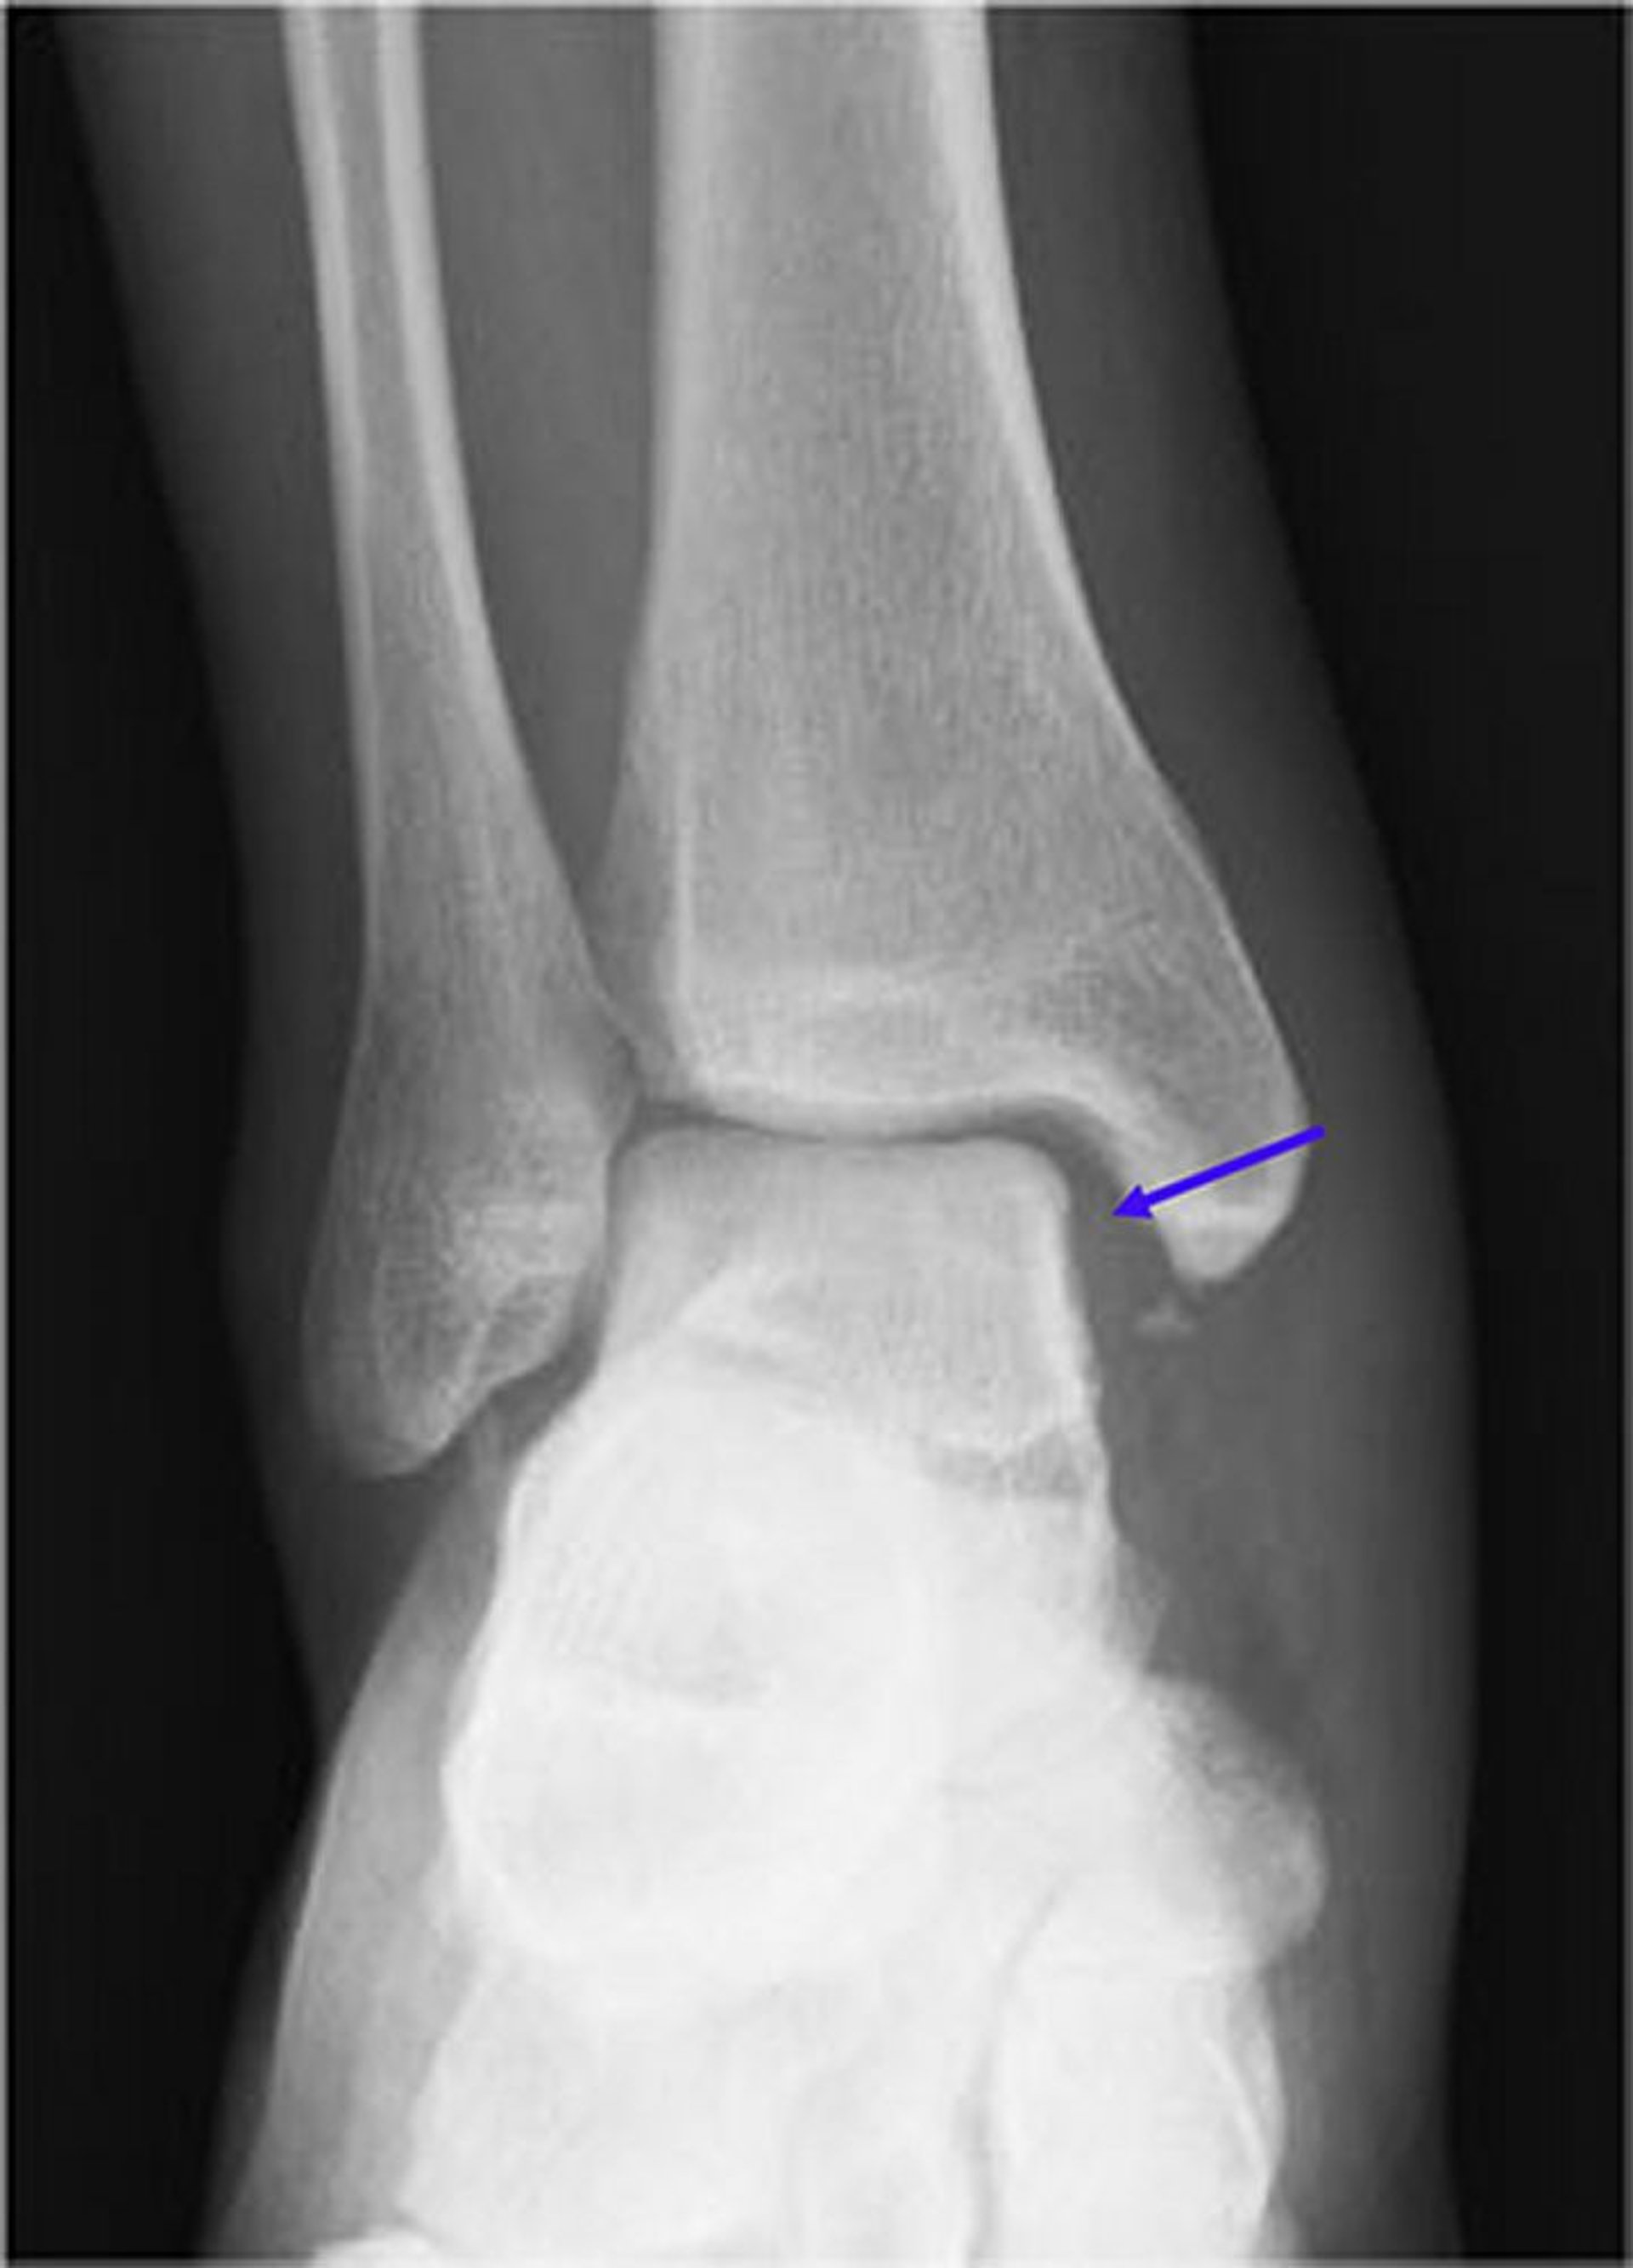

Fractura de Maisonneuve (1)

Esta radiografía muestra una alteración (ensanchamiento) de la articulación medial en mortaja (flecha azul). Normalmente, el espacio de la articulación en mortaja debe ser simétrico alrededor del astrágalo. En presencia de una fractura peroneal proximal concomitante, esto se conoce como fractura de Maisonneuve.

Image courtesy of Danielle Campagne, MD.